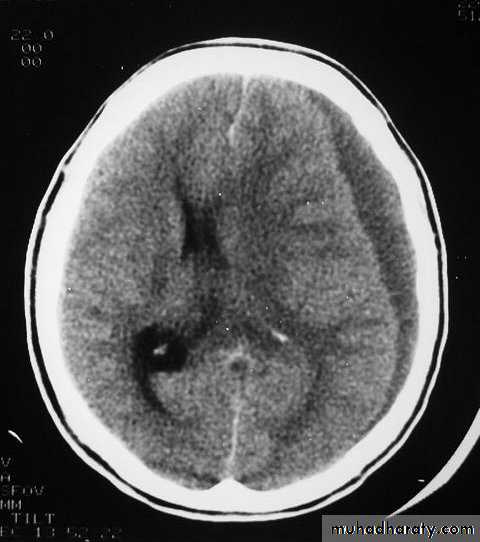

c. Intracerebral Haematoma

This is the least common of traumatic haematoma.

They are due to areas of traumatic contusion coalescing into a contusional haematoma.

Disrupted cerebral tissue release thromboplastins that potentiate haemorrhage.

CT scan: appear as hyperdence lesions with associated mass effect and midline shift.

Large intracerebral haematomas should be evacuated unless the patient’s neurological state is improving.

Small inracerebral haematomas may not require removal, but be aware that they can expand.